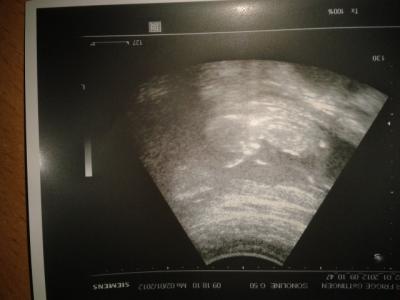

Hi danke Euch das ihr mir die Daumen gedrückt habt. Bei meinem Zwerg ist alles bestens. Hat am Daumen genukkelt sich am kopf gekratzt und war putz munter . Der Zwerg ist jetzt seit 7,9 cm ssl . Der Arzt war echt zufrieden. So nun zu meinen schmerzen , es ist mit aller Wahrscheinlichkeit mein Blinddarm. Ich soll schauen wie es mir in den nächsten Tagen geht und wenn es nicht besser wird muss ich mich beim Chirurgen vorstellen und schauen wie es weiter geht.Vielleicht ist es nur eine Reizung . Hattet ihr das auch schon mal ? So und nun Daumen drücken das es besser wird. Und nun noch ein Foto von meinem Zwerg

Bild zu Zurück vom Arzt ;-) - Forum für Juli - Mamis